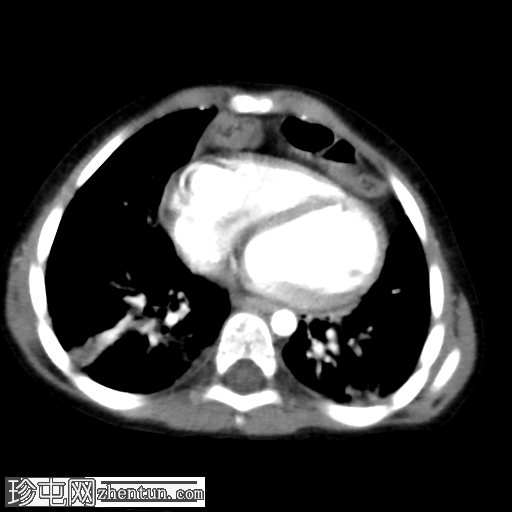

CT

3.png

冠状位增强扫描

动脉期

横结肠及其系膜经膈前部缺损疝入前纵隔。

未见肠管扩张或梗阻。

双肺实变影,提示呼吸道感染。